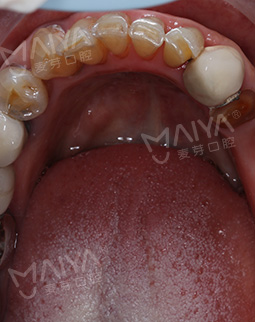

2019年4月15日 两个小时种好牙,一劳永逸享口福

今天来院种牙,肖阿姨满心欢喜地来到麦芽口腔,赵院长仅花了不到两个小时就为她种好了牙齿,种完牙后,肖阿姨竖起了大拇指:"种牙一点都不痛,打麻醉也很到位,用的针很小,我这么瘦都没什么感觉,胖一点更不会有。没有想象中可怕,整个过程很快,我也很放松,赵院长技术真的非常棒,术后没有不适感。"如今,肖阿姨看上去仿佛年轻了10岁,有了牙齿能够享口福了,生活也更加滋润。"现在有口福了,出去旅行才有意义。"说起种牙的愿望,肖阿姨说道。

为了确保种植手术的安全性,在种植术前,麦芽口腔宝安机构赵旭峰院长为肖阿姨做了全面检查,考虑到肖阿姨年龄大,又缺牙久,牙槽骨萎缩已经很严重。如果采用传统的种牙方法,不仅需要大量植骨,植骨后还需等待牙槽骨恢复,这将大大增加种植的时间。再三思索后,赵院长决定采用麦芽MAC数字化精确种植技术,这样仅需个别牙齿先植骨,再通过数字化导航技术精确植入植体就可恢复上半口牙齿。"来麦芽口腔果然没有错,年龄这么大,本来还担心能不能种,赵院长给我吃了一颗定心丸。"听完赵院长对方案的讲解后,肖阿姨心头的一块巨石终于落了下来。